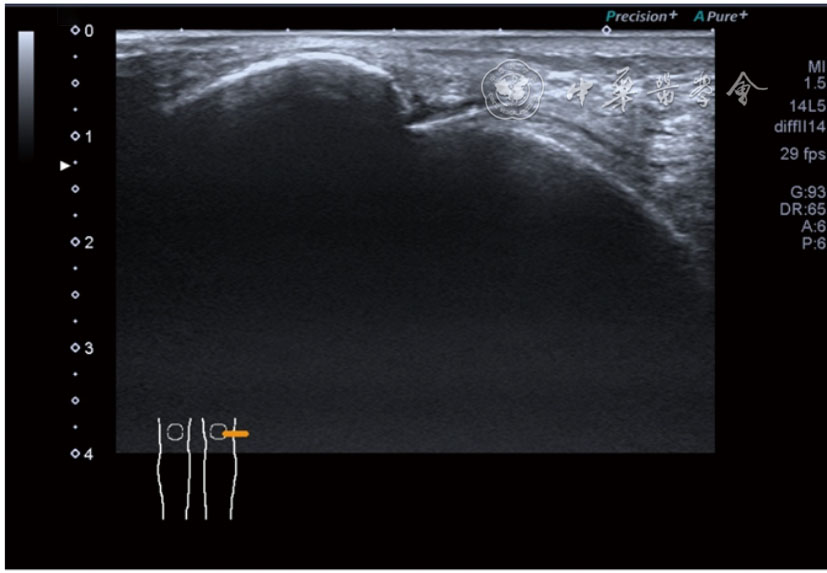

患者采取侧卧位,患肢在上,屈膝20°。应用10~18 MHz高频线阵探头,扫查深度1~3 mm。长轴和短轴结合双侧对比扫查。超声影像学所见:短轴可见卡压腓总神经近端增粗,面积增大;长轴可见腓总神经卡压处变细,其近侧肿胀、回声减低,而在卡压远侧则表现正常(图35);一些受压严重者可以出现神经周围积液,卡压神经部位的筋膜增厚(图36);受压神经内血流增加对临床诊断意义更大(图37);探头在病变神经处加压常可引起神经刺激症状。腓总神经支配的肌肉有失神经支配改变,表现为肌肉回声增高和肌肉萎缩(图38)。

图35 超声短轴可见卡压腓总神经近端增粗,面积增大;长轴可见腓总神经卡压处变细,其近侧肿胀、回声减低

图36 超声图像示腓总神经周围积液,卡压神经部位的筋膜增厚